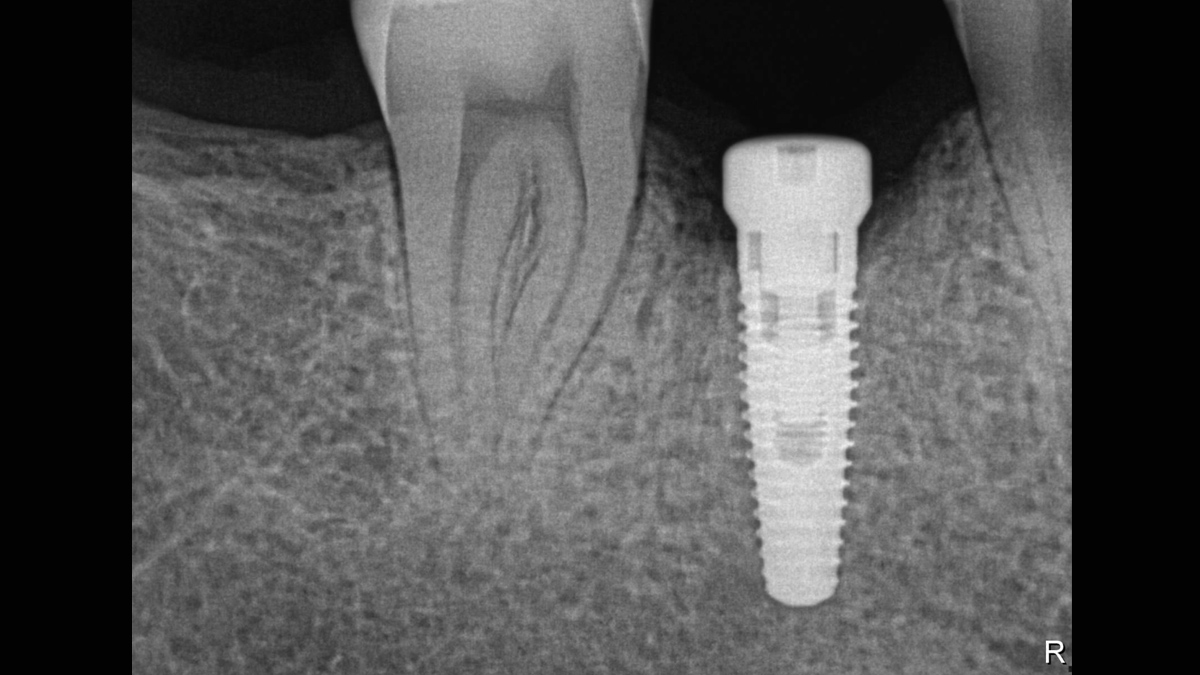

Xios XG Supreme proporciona una resolución teórica de 33 pl/mm y un tamaño de píxel de 15 μm que ofrece una excelente calidad de imagen sin el tiempo de espera adicional causado por un proceso de revelado o escaneo.

La excepcional calidad de las imágenes es solo el comienzo con los sensores intraorales Xios XG Supreme. El deslizador de nitidez dinámica le permite ajustar las configuraciones de su diagnóstico en términos de nitidez. Hay disponibles opciones adicionales del deslizador para modificaciones de brillo y contraste. Después de la configuración, las imágenes se muestran de manera eficiente para mejorar sus capacidades de diagnóstico, lo que le ahorra tiempo valioso. Un solo clic del mouse le permite obtener la imagen correcta para cada situación de tratamiento y mejor soporte clínico.

Los sensores Xios XG Supreme tienen cinco opciones diferentes de filtro: odontología general, endodoncia, periodoncia, restauración y caries. Estas vistas clínicamente específicas están diseñadas para optimizar su diagnóstico, mejorando la imagen para satisfacer sus necesidades.